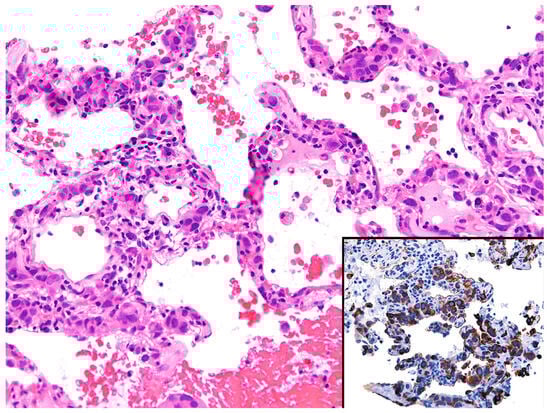

Histopathologic features in biopsies. IV-LBCL may be inconspicuous with only a few lymphoma cells seen within blood vessels, or it may show a patchy distribution (Figure 13).

Figure 13.

Intravascular large B-cell lymphoma (arrows). Inset: CD20 highlights the lymphoma cells within capillaries.

For these reasons, the diagnosis can be easily overlooked, and only a high index of suspicion will point to this diagnosis. On the contrary, cases with high tumor burden produce expansion of blood vessels that appear as alveolar septal expansion and may be interpreted as an interstitial pneumonic process [33]. The lymphoma cells show similar morphologic features to those described for DLBCL (centroblastic or immunoblastic) and are seen in the lumen of capillaries and of small- to intermediate-sized blood vessels. In some cases, the lymphoma cells are seen floating in the lumen, whereas in other cases, they may “pack” the entire blood vessel lumen, show “margination”, or may be admixed with fibrin or a thrombus [4]. IV-LBCL is positive for CD45, CD20, PAX5, CD79a, and bcl-2, with variable expression of CD5, CD10, bcl-6, and MUM1. CD15 and CD30 are usually negative (Figure 13). Most cases have a non-germinal center type immunophenotype, CD10−/bcl-6+/−/MUM1+. The lymphoma cells are negative for T-cell markers, ALK, EBER, keratins, and melanoma markers.